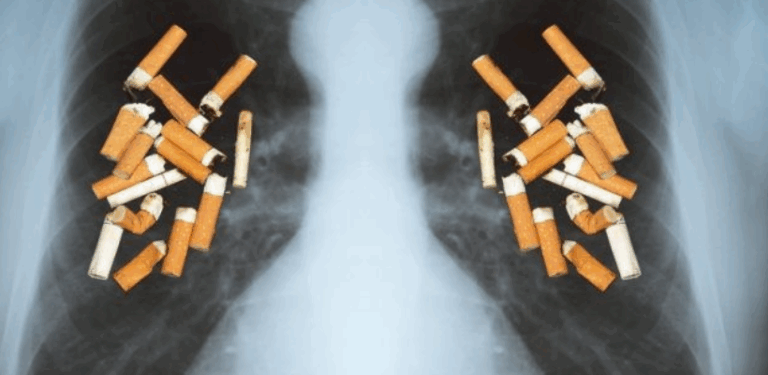

195 Është e rëndësishme të mbani mend se pirja e duhanit është një nga...